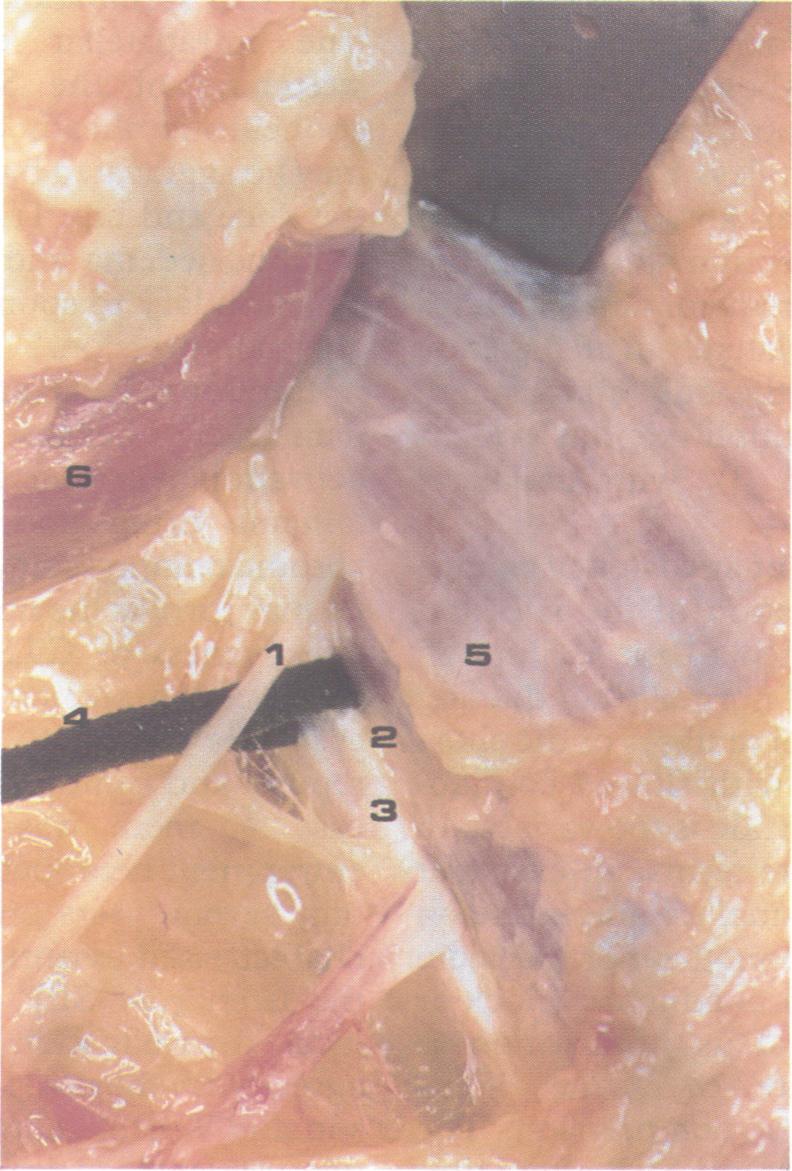

Neuralgia of the saphenous nerve (SN) is a rare clinical syndrome simulating a vascular disorder of the lower extremities. In four cases, the presenting complaint was persistent pain on the medial aspect of the knee. Examination revealed tenderness over the site of exit of the SN form the femoral canal. Femoral nerve motor conduction, quadriceps H-reflex and EMG of the leg muscles were normal. The sensory nerve action potential of the SN in the leg was not obtained in some patients, even in the unaffected leg. SEP were therefore preferred for diagnosis and performed at the infrapatellar and descending branches of the right and left SN and recordings from the Cz'-Fz electrode. Latency and amplitude differences were evaluated and compared with a control group of healthy subjects. An alteration in the SEP from one branch was observed on the painful side. Posterior tibial responses were normal. In one case, pain resolved immediately after neurolysis, confirming SN entrapment above the femoral canal, before its division. Pain resolved in two other cases and persisted in the last after medical treatment. SEP studies are valuable in the diagnosis of an isolated lesion of the SN.